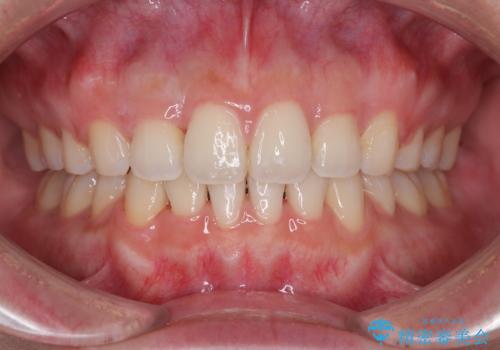

矯正歯科治療 → 上下顎前突(口ゴボ)

- 口元が出ているのを改善したい。 クリアブラケットによる抜歯矯正